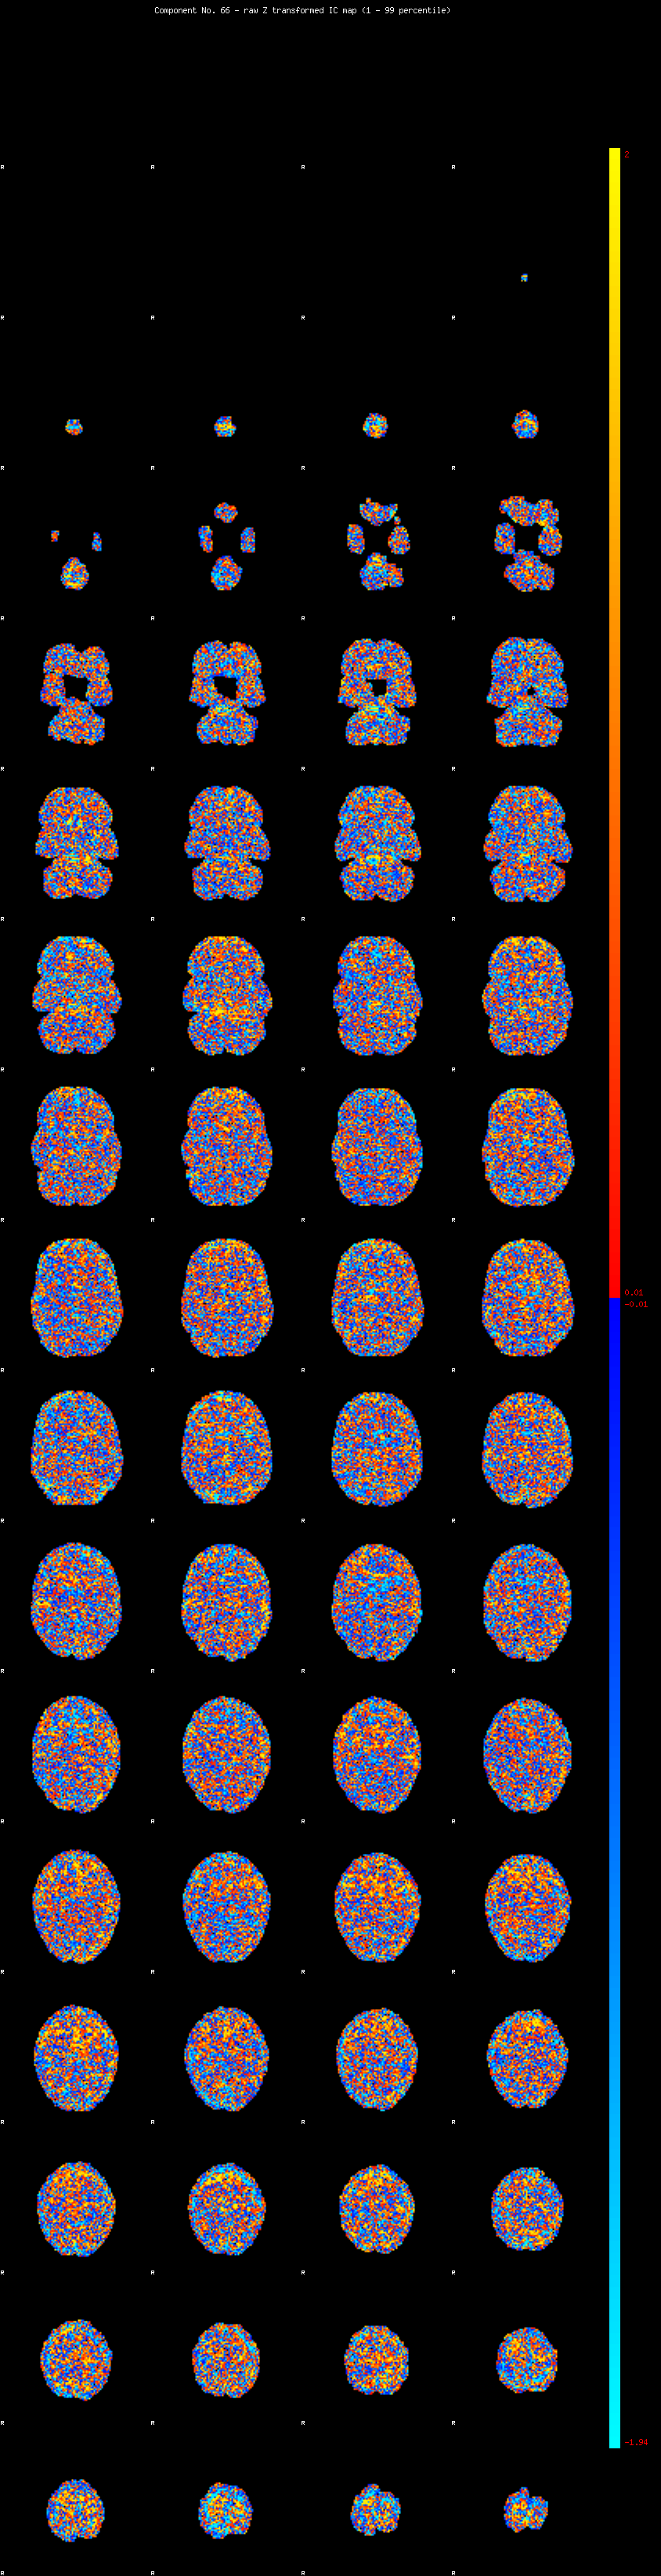

IC_66 Mixture Model fit

Means : 0.000000 2.044433 -2.006305

Vars : 1.000000 0.737991 0.659879

Prop. : 0.919838 0.043988 0.036174

This page produced automatically by MELODIC Version 3.14 - a part of FSL - FMRIB Software Library.